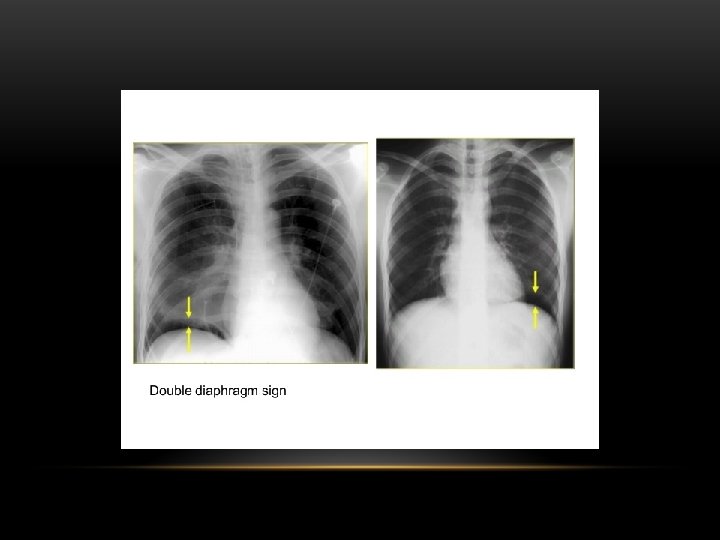

Pleural Effusion Fluid accumulates in the pleural space. Irrespective of the nature of fluid, radiologically they will look similar. Radiological criteria are: Density In dependent portion (Costophrenic angle in PA view). Blunting of costophrenic angle Lack of identifiable diaphragm (silhouette sign principle).

Lateral Decubitus : Most sensitive, may detect as little as 25 m. L

Pleural Effusion • Homogenous density • Loss of cardiophrenic angle • Loss of diaphragmatic and right cardiac silhouette

Supine projection erect projection